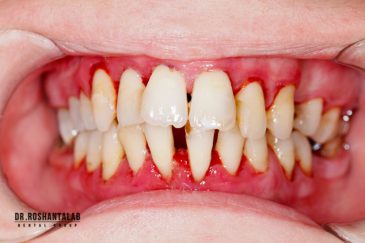

دکتر روشن طلب به همراه تیم دندانپزشکی خود درمان بیماران زیادی را به عهده دارند. بیمارانی که به علل مختلف از جراحی و دندانپزشکی می ترسند زمانی که تحت درمان جراح قرار می گیرند استرس قبل از حضور در مرکز و ناراحتی حین درمان به میزان قابل توجهی کاهش خواهد یافت و بعد از چند جلسه ترس از دندانپزشکی تا حدود زیادی از بین می رود.